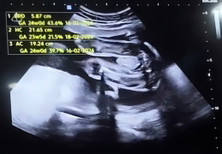

ทีมมกราค้าบ